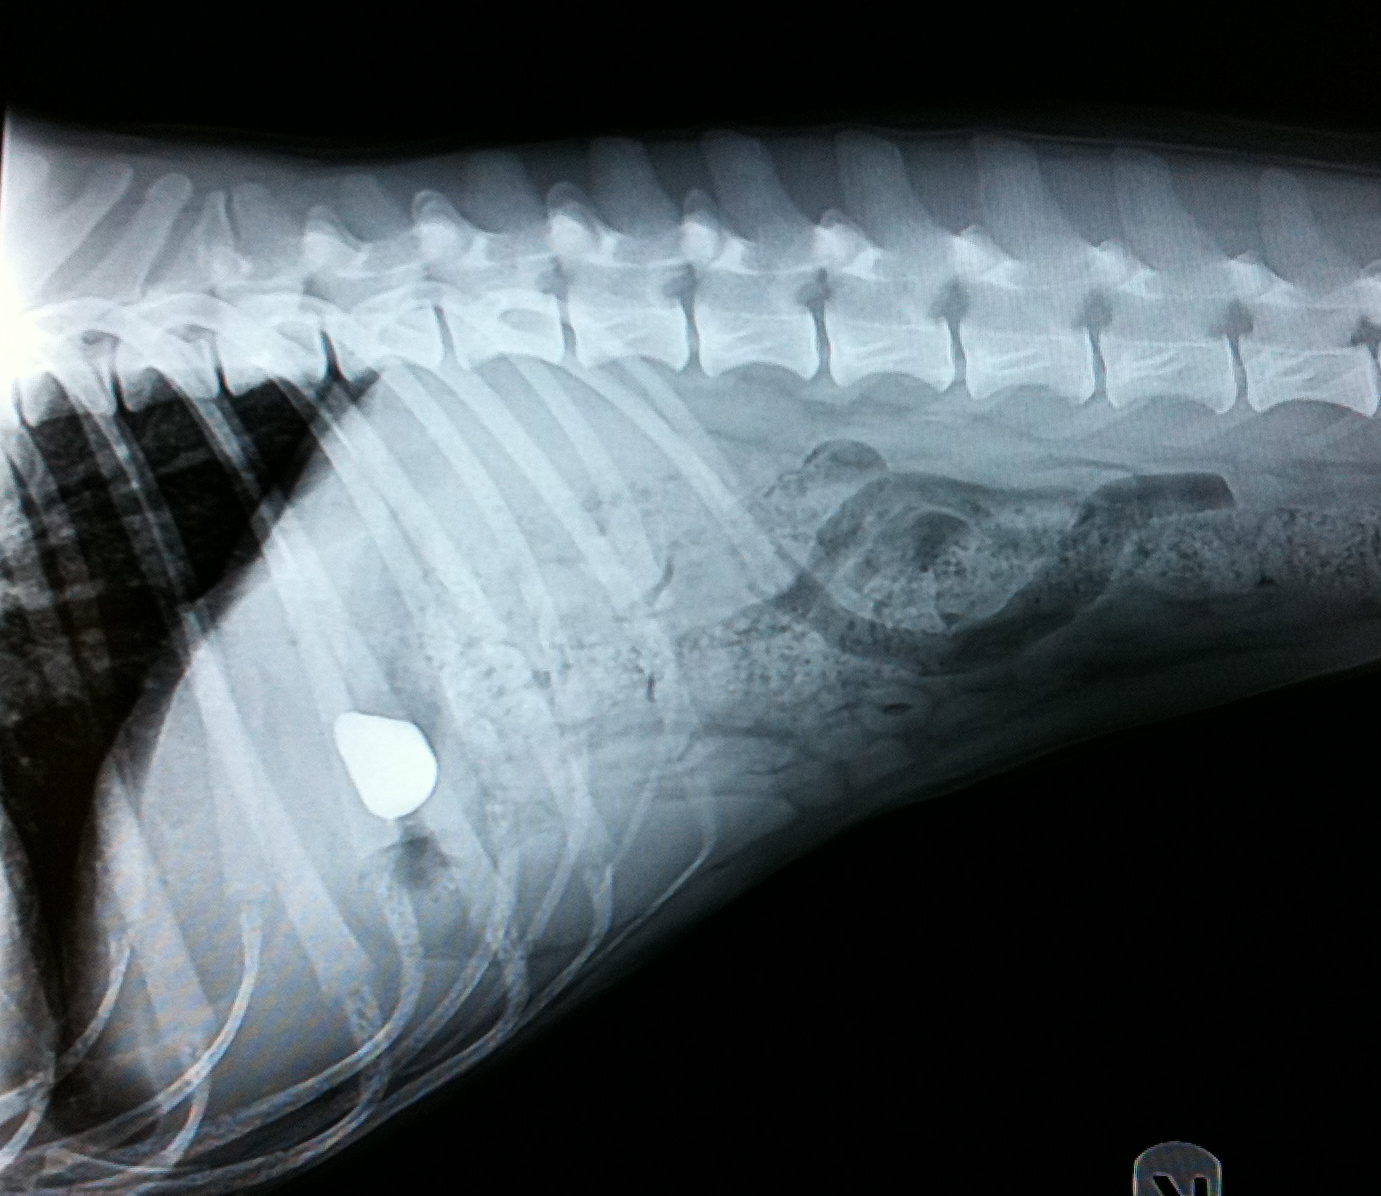

Gratitude